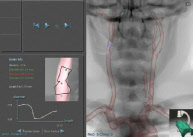

Real-time CT images

PROcedure Rehearsal Studio’s real-time CT images correspond to active fluoroscopic views to help you understand your patient’s anatomy and to assist in effective CT interpretation and study.